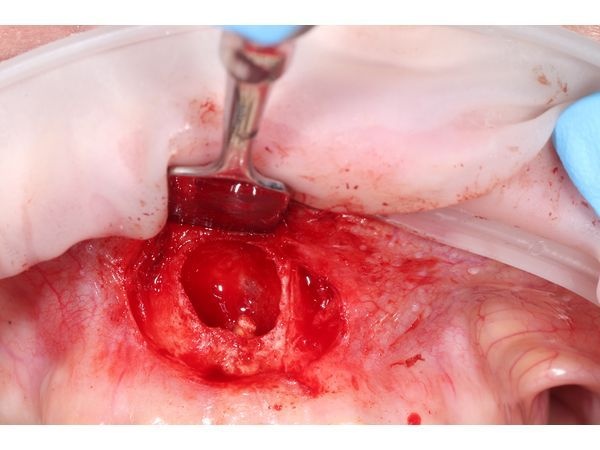

- создали окно для доступа к верхушке корня с помощью бормашины;

- пинцетом аккуратно извлекли кисту вместе с оболочкой и остатками пломбировочного материала за верхушкой корня;

- удалили верхушку корня и запломбировали оставшуюся верхнюю часть Триоксидентом;